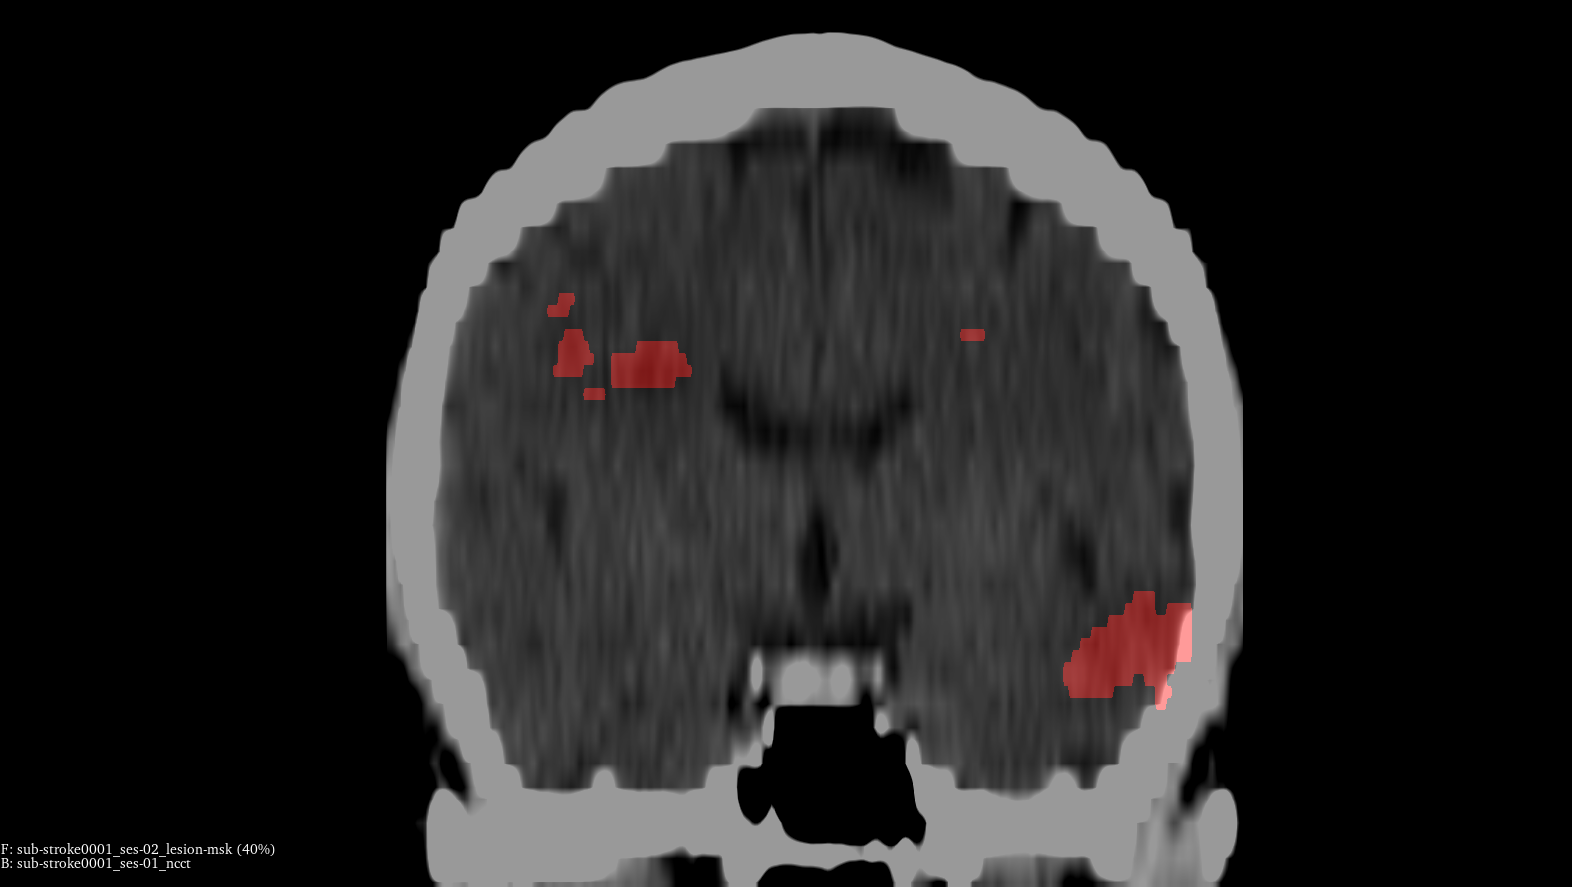

Clinical AI for Stroke Imaging

a deep learning research project for medical imaging